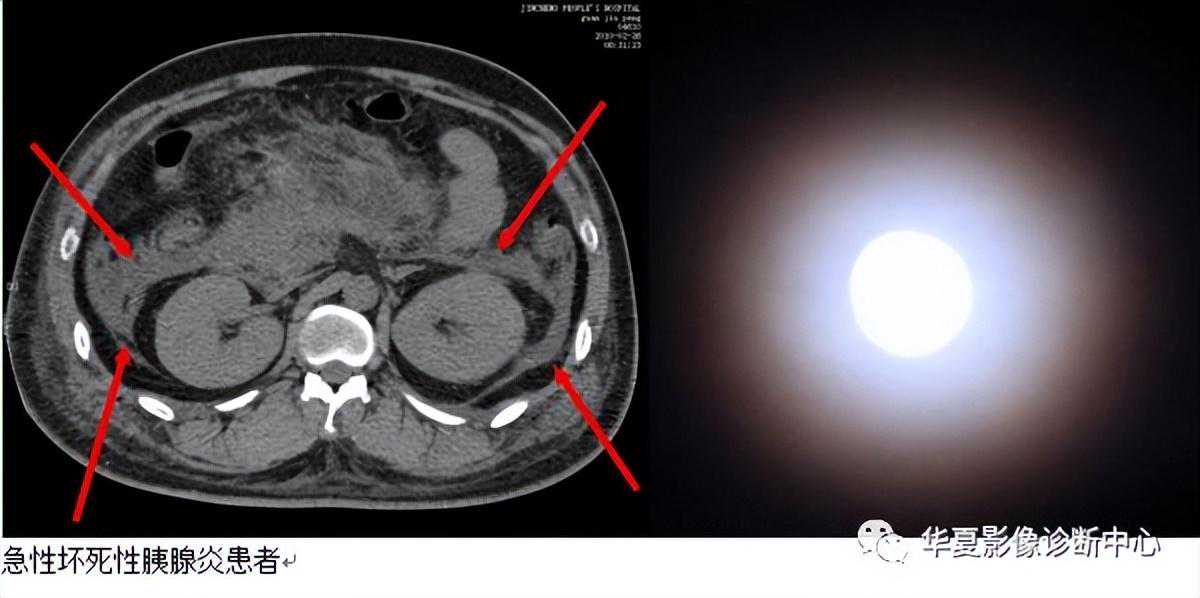

【影像表现】CT上肾前筋膜增厚,肾前旁间隙渗出、积液,肾周间隙内脂肪密度被月晕状低密度影代替,低密度影CT值较高,可25Hu。

【征象解释】肾周晕征是急性坏死性胰腺炎(ANP)并发症的CT征象之一,急性坏死性胰腺炎疏松结缔组织炎由含蛋自酶的胰液外滋引起,常发生在胰尾,表现为肾前筋膜增厚。穿破肾筋膜累及肾周脂肪层,形成肾周晕征。

【讨论】急性胰腺炎病理学上分为2型:1)急性水肿型(间质型〕,较为常见,约占90%,胰腺呈弥漫性或局限性水肿,体积增大,间质水肿、充血和炎性细胞浸润。可有胰腺周围脂肪坏死,但无胰实质坏死改变。2)急性坏死型(出血型)。胰实质内腺泡和胰腺周围脂肪组织大片坏死,伴血管坏死出血,是本症的特点。腹腔内大量血性渗液,由于渗透液中含有大量胰脂酶,因而使网膜、腹膜及其他脂肪组织也大片坏死,此型病死率达50%。急性坏死性胰腺炎(ANP)可发生胰腺灶性或弥漫性坏死,并继发假性囊肿形成、感染、休克以及多器宫功能衰竭综合征等严重的并发症,病死率高。早期诊断ANP,早期评估胰腺坏死程度及严重度分级。并及时发现其并发症,是降低ANP病死率和提高生存率的关键。多排螺旋CT的出现及各种三维重建技术的应用,对ANP的评价优势更是日益突出,可反映胰腺及周围局部的情况,如胰腺实质有无坏死、胰周及腹膜后炎性扩散的范围、有无并发症等情况,为临床ANP诊断及治疗提供丰富信息。急性坏死性胰腺炎的CT诊断依据:

1)胰周积液CT值15hu,系单纯的胰周积液;如ct值较高,25Hu,是伴有脂肪坏死的指征;

2)胰腺内低密度影,CT值可降为0~22Hu;

3)增强CT示不强化区3cm或胰腺受累区30%,表现为点状、斑片状及大片状,如有出血时可见高密度影夹杂在低密度影中;

4)坏死的范围可分为弥漫性、局灶性和多发性。评估急性胰腺炎预后最常采用Balthazar分级标准:A级—胰腺正常;B级—胰腺肿大,弥漫性或局限性增大,密度不均或有小区域的积液,轮廓模糊,但不伴有胰周积液;C级—炎症蔓延至胰周。除胰腺实质异常外伴有胰周积液及胰周脂肪密度异常;D级—炎症扩散至胰外1个间隙,示境界不清的积液试和炎性肿块;E级炎症扩散至胰腺邻近2个以上的区域,示积液或积气。程燕等报道胰腺坏死.与腹膜后扩散范围的关系;根据Balthazar等的文献报道,胰腺坏死程度与腹膜后炎性扩展范围是急性胰腺炎的2个重要顶后指标。

在胰腺坏死50%的急性坏死性胰腺炎中,腹膜后炎性扩展范围分级达E级的占70%,统计发现急性坏死性胰腺炎胰腺坏死程度与胰周、腹膜后炎性扩展的范围大小之间存在着统计学意义上的关联性。其趋势是坏死程度越重,腹膜后炎性扩展范围分级越大,反之亦然。